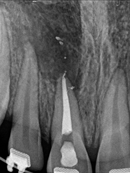

Root Canal Cases